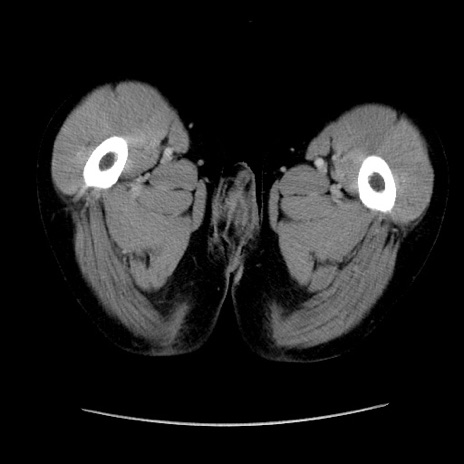

症例37(横断像)

【症例】40歳代 男性

【主訴】腹痛

【現病歴】4時間ほど前に電車に乗車中に臍部上より腹痛出現。徐々に増悪し起立困難となり、救急外来受診。生ものは数日食べていない。今朝お雑煮を食べた。

【身体所見】BT 36.8℃、BP 117/84mmHg、HR 91/min、SpO2 97%、苦悶様、腹部:臍上部広範囲圧痛あり、反跳痛±

【データ】WBC 8100、CRP 0.03